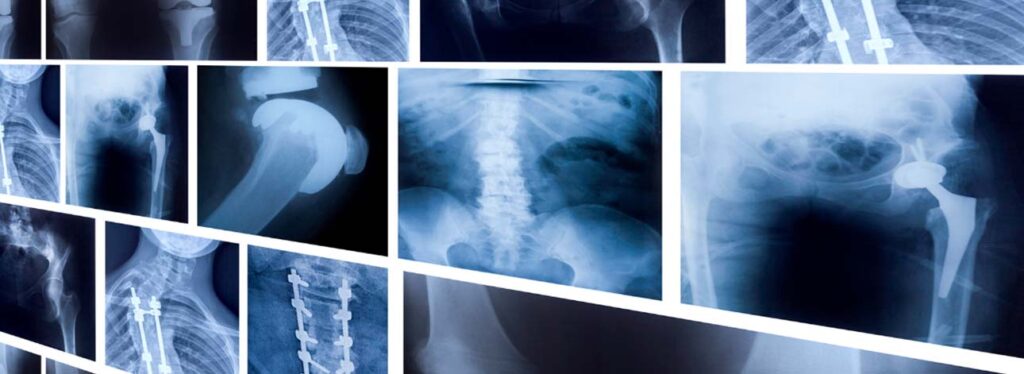

Os exames de Raio-X ou Radiografia não são invasivos e auxiliam no diagnóstico de fraturas, alterações pulmonares e outras condições. O equipamento faz uso da radiação para atravessar órgãos e tecidos gerando imagens da região de interesse para o médico.

Deste modo, pelo fato do corpo humano apresentar diferentes densidades nos tecidos, os raios-x geram imagens distintas. Vale ressaltar, que a radiação não atravessa os ossos, por isso, as imagens geradas apresentam coloração branca. Já em estruturas moles ou que apresentam ar, com os pulmões apresentam coloração preta.

A ferramenta é usada para identificar lesões nos ossos e também analisar doenças no aparelho gastroesofágico. Além disso, no pulmão os médicos podem diagnosticar doenças como pneumonia ou derrame pleural, indicadas por manchas esbranquiçadas.